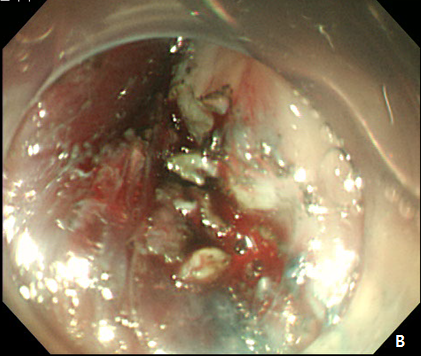

Figure 3 Endoscopic treatment of esophageal stricture.

(A) A follow-up esophagogastroduodenoscopy (EGD) at 1 month after the procedure revealed significant stricture at esophagus. (B) Repeatitive endoscopic balloon dilation was performed. (C) After 8 times of endoscopic ballooning, esophageal stricture was resolved.